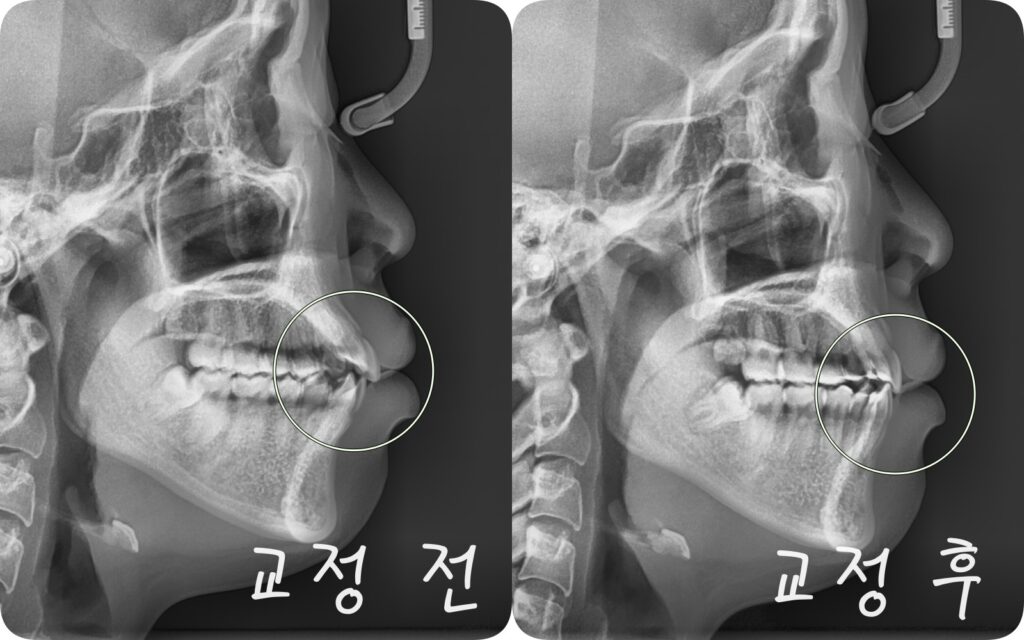

측방사진에서 보면 입술이 전방으로 돌출된 양상을 보이며 상악 전치가 전방으로 미세하게 기울어져있음을 알 수 있죠.

중랑구 교정치과 에서 이는 상하악 전후방 관계의 불균형이 동반된 골격성 2급부정교합으로 판단되는데

이러한 경우에는 부족한 공간 확보와 돌출된 상악을 후방으로 이동시키기 위한 발치교정이 필요할 수 있습니다.

교정이 완료된 후 가지런한 치열이 완성되었으며 그로인해 높은 심미성을 회복합니다.

초진시 문제가 됐던 총생과 돌출입도 발치교정으로 개선되었는데 방사선 사진을 통해 그 변화를 확연히 알 수 있습니다.